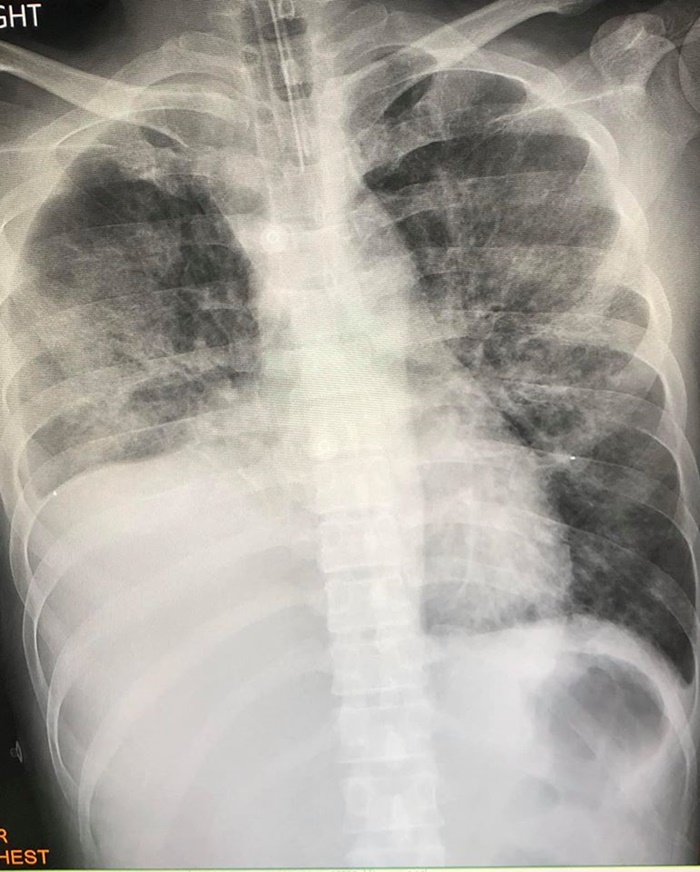

อาการไม่ดีขึ้น เมื่อเอกซเรย์ปอดก็พบว่ามีฝ้าขาวทั้งสองข้าง

ส่วนปอดเดิมที่เป็นมะเร็ง ก็พบว่าก้อนมะเร็งมีขนาดใหญ่กว่าเดิม

เมื่อส่งตรวจทางห้องปฏิบัติการก็วินิจฉัยได้ว่าเป็นปอดอักเสบจากการใช้กัญชาด้วยบุหรี่ไฟฟ้า

จึงเริ่มให้สเตียรอยด์ตั้งแต่วันที่ 20-22 พฤศจิกายน ที่ผ่านมา